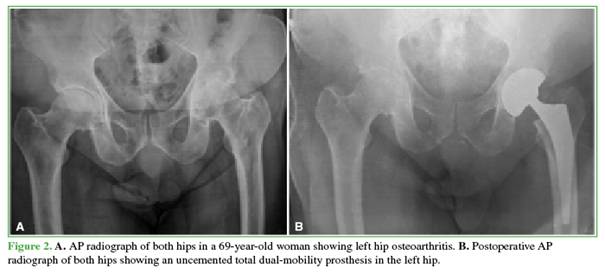

A descriptive, retrospective study was conducted, reporting preliminary results at 2 years of follow-up, in a series of patients treated with primary THA using a dual-mobility cup at a single center (a tertiary-care institution in the public health system of the Autonomous City of Buenos Aires) between January 2014 and December 2019 (Figures 1 and 2).

A total of 61 patients (30 women and 31 men) underwent THA with a dual-mobility acetabular cup system [cemented, n = 17 (27.9%); hybrid, n = 10 (16.4%); uncemented, n = 34 (55.7%)]. The mean age was 62.5 years. The following underlying conditions were recorded: hip osteoarthritis (36 cases, 59%), subcapital hip fracture (17 cases, 27.9%), and avascular necrosis of the hip (8 cases, 13.1%). Demographic characteristics are shown in Table 1.